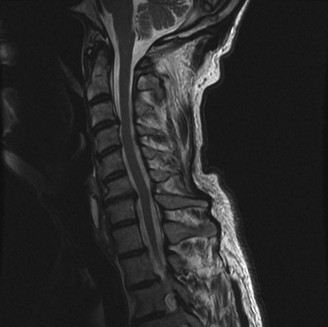

CASE 1 A 63-year-old male sustained a hyperextension injury to his neck while diving into a pool. Upon presentation, he reports decreased sensation in his hands and decreased strength in his arms and wrists, but no lower extremity complaints. On motor examination, he has 5/5 strength in his deltoids and elbow flexors and 4/5 strength in the elbow extensors, wrist extensors, and finger flexors. Lower extremity motor examination is normal. Sensation is decreased to light touch in both hands. Otherwise his sensation is preserved. Images of his cervical spine are shown in Figures 1–1 to 1–3.

Figure 1–1

The correct answer is (B). The clinical scenario describes a patient with central cord syndrome (CCS). CCS continues to be the most common incomplete spinal cord injury accounting for 15.7% to 25% of all spinal cord injuries. The characteristic presentation is an extension moment injury in a previously spondylotic and stenotic spine. Figures 1–1 to 1–3 demonstrate a spondylotic spine with central narrowing and CSF effacement that is worst at the C3–4 level. Bleeding, edema, and/or Wallerian degeneration lead to damage of the lateral corticospinal tract which is the main descending motor tract in the spinal cord. The more central anatomic position of the homunculus to the upper extremities places them at greater risk than those to the lower extremities. As such, injury to the lateral corticospinal tract is characterized by upper more than lower extremity involvement and motor deficits being more pronounced than sensory deficits.